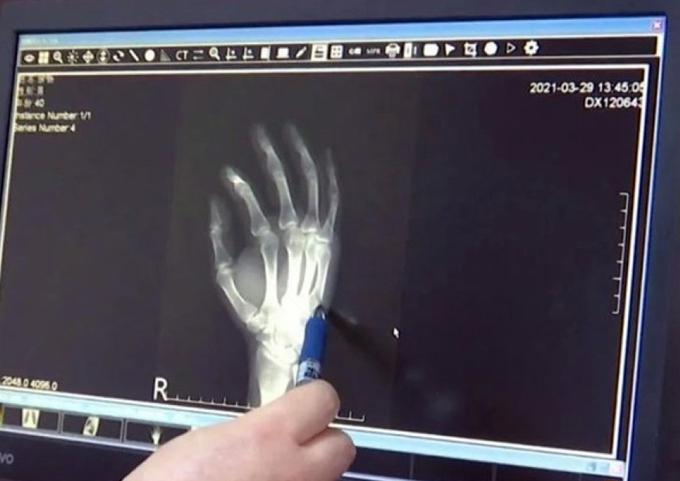

05/04/2021 20:59Ông bố gãy tay vì đập bàn khi dạy con học

Các bác sĩ ở thành phố Trường Sa, tỉnh Hồ Nam gần đây cho biết có một bệnh nhân họ Xu đã tới khám sau khi thấy bàn tay bị bầm tím và đau mãi không khỏi. Kết quả chụp chiếu cho thấy xương ở bàn tay phải của anh này đã bị gãy sau một cú đập xuống bàn.

Theo truyền thông địa phương, anh Xu kể rằng tự làm mình bị thương trong khi dạy con học. Con của anh nhiều ngày không chịu làm bài và không chịu nghe bố giảng. Tức giận và không có nơi nào để trút, Xu đã tự làm đau chính mình và "cái bàn".

Xu cho biết lúc đó anh đã nắm bàn tay phải, đập mạnh xuống bàn. Sau cú đập, bàn tay anh lập tức phồng lên và tím tái. Theo bác sĩ, xương ống tay ngón út của Xu bị gãy và cần phải cố định. Trường hợp của Xu, nếu không được chữa trị kịp thời còn có thể gây biến dạng bàn tay, ảnh hưởng đến chức năng bình thường của tay.

Sau khi biết bố bị gãy tay, con của Xu cảm thấy có lỗi và tự trách bản thân. Xu cho rằng nếu từ giờ trở đi mà con anh ngoan ngoãn, nghe lời thì vết thương của anh rất đáng giá. Mặc dù vậy, Xu cũng khuyên các bậc phụ huynh không nên phạm sai lầm tương tự mình.